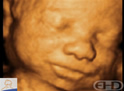

6 months, 2 weeks

Source: CREATE Fertility, London, UK.

All ages referenced to fertilization, not last menstrual period. One month = 4 weeks.

4D Ultrasound